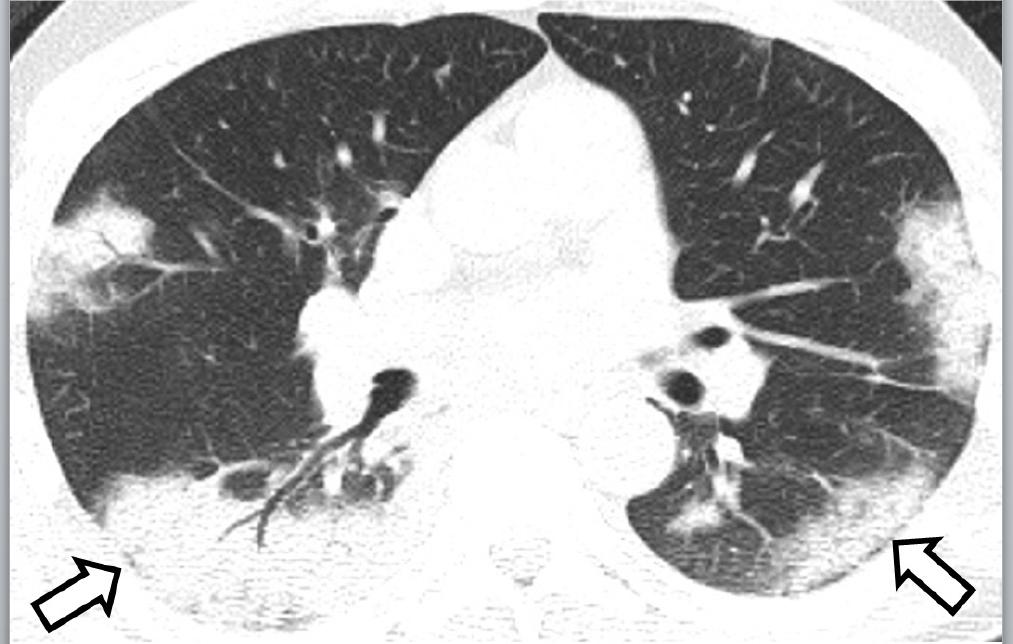

En la tomografía simple de tórax realizada al ingreso de cada paciente, los patrones más comunes fueron los siguientes: opacidad de vidrio esmerilado de predominio periférico y subpleural (Figura 1), encontrado en 15.9 % de los hombres y 20 % de las mujeres; la consolidación, con predominio hacia los segmentos posterobasales (Figura 2); así como los patrones de empedrado y mixto, forma concomitante de los mencionados (Figura 3). En los diagramas de Venn (Figura 4) se representan los porcentajes de las diferentes combinaciones de patrones.

Figura 2 Hombre de 47 años con neumonía causada por SARS-CoV-2. Se observa patrón de consolidación, predominantemente en segmentos posterobasales de forma bilateral (flecha).